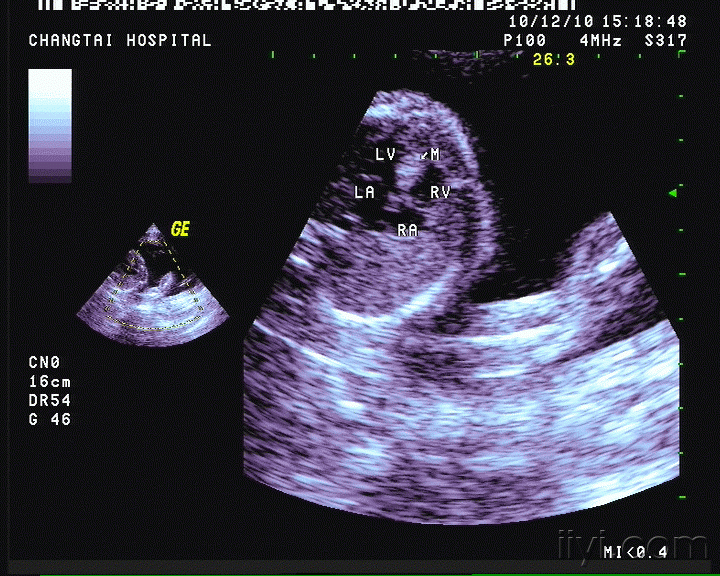

横纹肌瘤的超声心动图诊断及典型病例分享

胎儿心脏横纹肌瘤?